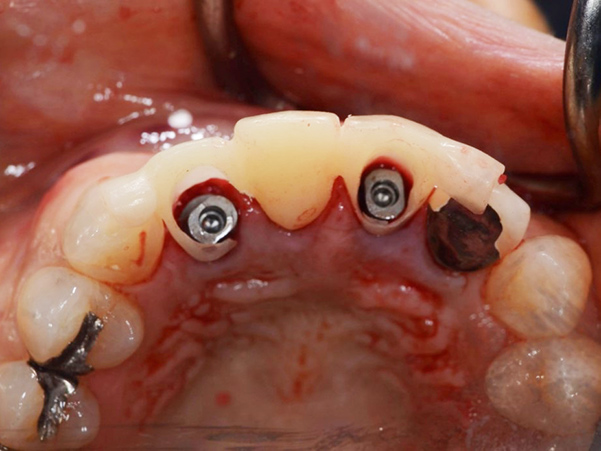

1次手術時の流れ

①手術開始時

②被せ物を外した状態

③抜歯

④サージガイドを使用したインプラント体の埋入

⑤インプラント体を埋入した状態

⑥仮歯を製作していく段階

⑦仮歯を装着した状態

埋入したばかりのインプラント体に負担がかからないように、下の歯と当たらないような形と噛み合わせになるよう調整しています。